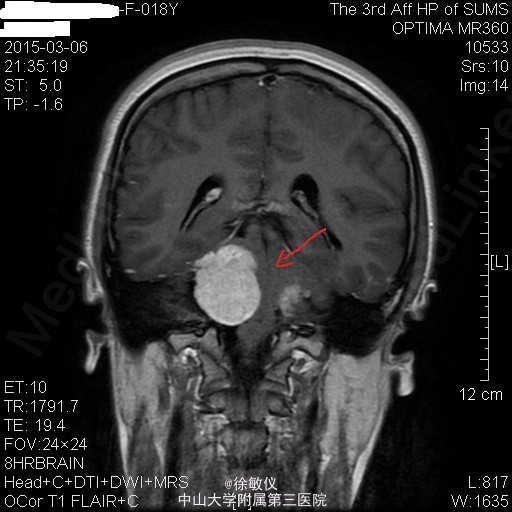

青年女性,主诉:左侧面部麻木,右侧听力下降半年。

查体:神清,查体合作,对答切题。颈软,无抵抗。左侧面部浅感觉痛觉过敏。双侧眼球运动正常,双侧视野粗测无缺损。右侧听力粗测听力下降。双侧瞳孔等大等圆,直径3mm,对光反射灵敏。双侧肢体肌力5级,肌张力正常。病理征未引出。 辅查:头颅MR提示:双侧桥小脑角区、鞍上池右侧、左侧三叉神经颅内段及枕部多发占位,考虑为神经纤维瘤病II型。

诊断:双侧听神经鞘瘤 排除手术禁忌症后,在全麻下行显微镜下经右侧乙状窦后入路右侧桥小脑角区占位病变切除术,术程顺利。术后于SICU监护治疗1天后顺利转回我科,予抗感染、脱水降颅压、营养支持及对症治疗,患者恢复良好。 术后病理诊断:(桥小脑角占位)形态结合免疫组化结果,符合神经鞘瘤。免疫组化结果(⑥):S100(+),Vim(+),Ki-67(1%+)。 术后复查头颅MR示:1、右侧听神经瘤术后改变,右侧桥小脑角区占位大部分已切除,术区少量积液同前;左侧侧脑室内少量积血,基本同前。 2、左侧桥小脑角区、鞍上池右侧、左侧三叉神经颅内段及枕部多发占位同前,考虑神经纤维瘤病。